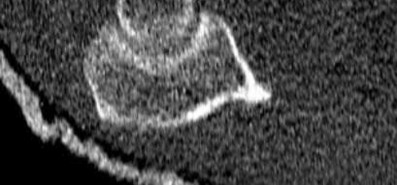

What physical exam finding is most likely to be found in association with the injury shown in Figures A and B?

The x-ray shows a fracture of the anteromedial facet of the coronoid with an intact radial head. Large anteromedial facet fractures are associated with varus posteromedial rotatory instability.

The anteromedial facet of the coronoid provides support to the medial elbow against varus stress. Varus and posteromedial force applied to the elbow results in disruption of the lateral collateral ligament (LCL) from its proximal origin. The coronoid is fractured as it is forced against the medial trochlea.

Coronoid fractures of significant size involving the sublime tubercle (insertion of medial collateral ligament) result in varus instability.

Figure A is an AP view of an elbow with an anteromedial facet of the coronoid fractured. The lateral joint space is widened due to injury to the LCL. The medial joint space is narrowed and collapsed. A lateral view is shown in Figure

B. Illustrations A and B show AP and lateral views of a coronoid fracture fixed with buttress plating. The LCL origin was fixed with a suture anchor. Illustration C shows the O'Driscoll classification of coronoid fractures. Illustration D lists injury patterns that suggest posteromedial versus posterolateral rotatory instability.